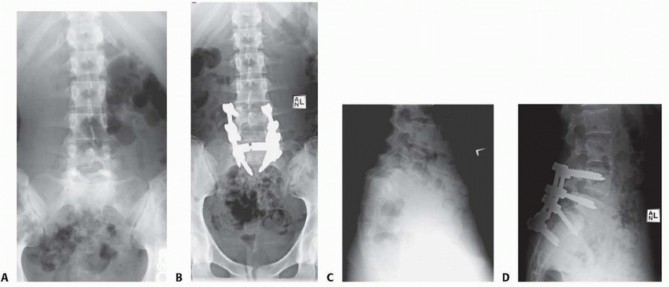

High-quality radiographs are taken immediately postoperatively to ensure proper graft and instrumentation placement before the patient is taken out of the operative room (

FIG 5

).

FIG 5 • Radiographs from a 17-year-old girl with high-grade isthmic spondylolisthesis who underwent decompression, reduction, and instrumented fusion. A,C. Initial PA and lateral radiographs showing the preoperative deformity. B,D. PA and lateral films showing postoperative correction using the CHOP technique.

*